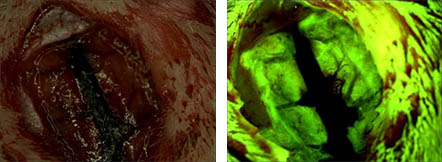

荧光:对样品做荧光标记来进行观察,主要做物质鉴定,如抗体、抗原、荧光原位杂交(FISH)等

— 荧光 —

荧光原位杂交技术(fluorescence in situ hybridization),简称FISH,是利用荧光标记的特异核酸探针与细胞内相应的靶DNA分子或RNA分子杂交,通过在荧光显微镜下观察荧光信号,来确定与特异探针杂交后被染色的细胞或细胞器的形态和分布,或者是结合了荧光探针的DNA区域或RNA分子在染色体或其他细胞器中的定位。